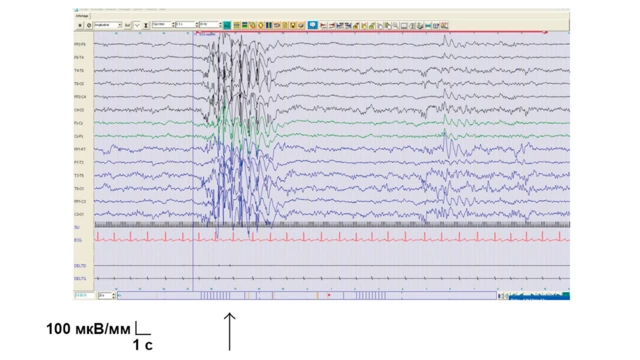

- Электроэнцефалография (ЭЭГ) – основной диагностический метод при эпилепсии. Известно, что у больных с эпилепсией имеются нарушения в характере мозговых волн. Эти изменения можно зарегистрировать даже при отсутствии приступов. Как правило, изначально проводят ЭЭГ-видеомониторинг в ночное время. Это позволяет установить причину эпилептических припадков. Затем делаются обычные ЭЭГ 1 раз в полгода4.